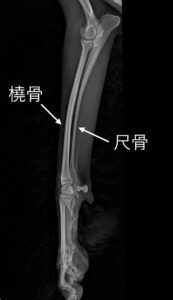

ー“橈尺骨骨折”とは?

橈尺骨とは、前足の肘から手首までの2本の細い骨(橈骨と尺骨)のことです。

この部分は特に小型犬や子犬では骨が細く、衝撃に弱いのが特徴です。

もちろん個体差はありますが、小さい子だと骨の太さが5mmもない子もいます。